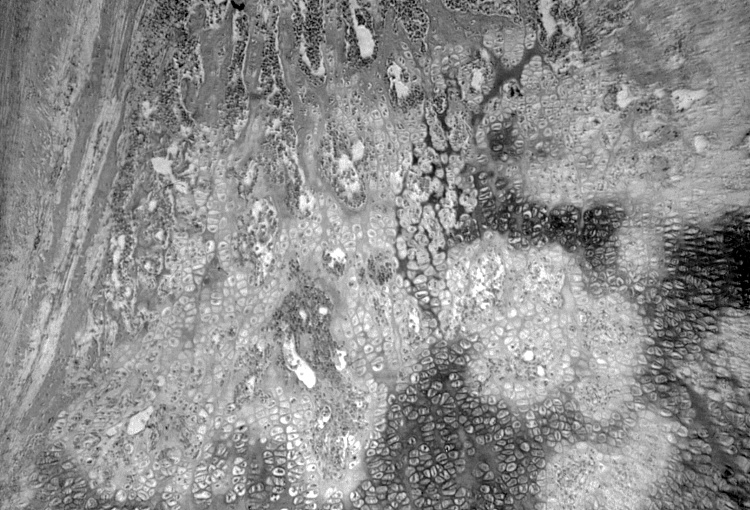

显微镜下观察到的梅毒照片。

基于这种如今看来十分荒谬、当时却被美国卫生界认为理所当然的理论,美国公共卫生局(USPHS,United States Public Health Service)从1932年起和美国疾控中心(CDC)联手,借助阿拉巴马州历史悠久的塔斯基吉研究所(Tuskegee Institute),开展专门针对黑人的、一项令人发指的试验。

他们在不告知真实目的的情况下,以“免费治疗坏血病”为诱饵,诱骗600名25-60岁、来自阿拉巴马州梅肯县的贫困黑人男子参加梅毒治疗试验,在长达40年的时间里共有399人因体内含有潜伏梅毒病毒被选入“实体观察组”参加试验,其中28人直接死于梅毒,100人死于梅毒并发症,40人妻子受传染,1人的子女出生时就患上梅毒,而其余201人未感染梅毒病毒,被作为“对照组”加以观察。之所以如此,完全由于患者受欺骗,误以为得到治疗,而试验方有意不提供真正的治疗,以确保数据连贯性所致。

这些“人试”包括针对受试者的血液检查、X光检查、脊椎穿刺和尸体检查(如果他们死去),而给他们服用的所有药物,其实都是不具备任何疗效的安慰剂。在当时,青霉素(penicillin)早已被证明是最有效的梅毒治疗药物,而美国则是最大的青霉素生产国,但在正式试验期间竟无一名受试者被注射了青霉素。在一些天良未泯的参与研究者推动下,直到1952年才有约30%幸存者获得了青霉素治疗。